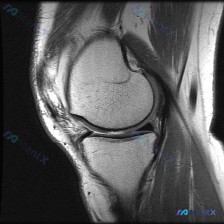

病例基础信息 这是一份特殊的膝关节影像评估需求:输入描述提示存在软骨异常 (Chondral abnormality),提供1张膝关节矢状位MRI静态图像,我们先看影像学分析结果: 影像学观察结果 1. 骨骼与软骨:股骨远端、胫骨近端、髌骨骨皮质完整,无骨折,无骨髓水肿;股骨髁、胫骨平台、髌股关节面...

看到这张膝关节MRI读片的需求,问题是观察到「软骨异常」,我整理了一下完整的病例资料和分析思路,和大家分享讨论。 一、影像基本信息 这是一张膝关节矢状位T1加权MRI影像,图像对比度尚可,解剖结构清晰,无明显运动伪影,层面接近膝关节中间矢状面,完整显示股骨远端、髌骨、膝关节间隙及胫骨近端结构。 二、...